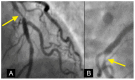

Background: In the study of coronary artery disease, the mechanisms underlying atherosclerosis initiation and progression or regression remain incompletely understood. Our research conceptualized the cardiovascular system as an integrated network of pumps and pipes, advocating for a paradigm shift from static imaging of coronary stenosis to dynamic assessments of coronary flow. Further review of fluid mechanics highlighted the water hammer phenomenon as a compelling analog for processes in coronary arteries. Methods: In this review, the analytical methodology employed a comprehensive, multifaceted approach that incorporated a review of fluid mechanics principles, in vitro acoustic experimentation, frame-by-frame visual angiographic assessments of in vivo coronary flow, and an artificial intelligence (AI) protocol designed to analyze the water hammer phenomenon within an acoustic framework. In the analysis of coronary flow, the angiograms were selected from patients with unstable angina if they had previously undergone one or more coronary angiograms, allowing for a longitudinal comparison of dynamic flow and phenomena. Results: The acoustic investigations pinpointed pockets of contrast concentrations, which might correspond to compression and rarefaction zones. Compression antinodes were correlated to severe stenosis, due to rapid shifts from low-pressure diastolic flow to high-pressure systolic surges, resulting in intimal injury. Rarefaction antinodes were correlated with milder lesions, due to de-escalating transitions from high systolic pressure to lower diastolic pressure. The areas of nodes remained without lesions. Based on the locations of antinodes and nodes, a coronary acoustic action map was constructed, enabling the identification of existing lesions, forecasting the progression of current lesions, and predicting the development of future lesions. Conclusions: The results suggested that intimal injury was likely induced by acoustic retrograde pressure waves from the water hammer phenomenon and developed new lesions at specifically exact locations.